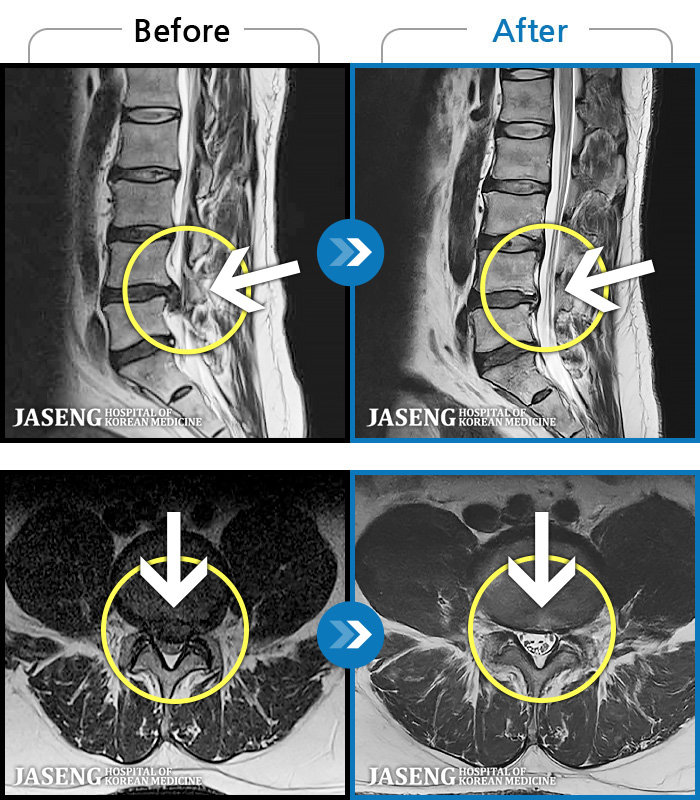

[Կñ:22.08.30~24.08.05]

[_㸮ũ] ٸ ߳ .

No.118

ȸ 459

2024.12.24